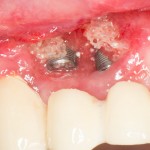

Случается чаще, чем можно представить. В основном, из-за убеждения ряда моих коллег в том, что конечная цель имплантологического лечения — это интегрированные импланты, а не протезирование на этих самых имплантах. Итог — ну вот, всё прижилось, пациент приходит к ортопеду, а тот разводит руками — типа, ничего не могу сделать. С одной стороны, ортопеда можно понять — на кривом фундаменте хороший дом не построишь. С другой стороны, некоторые имплантологи считают, что ортопеды просто неженки и лентяи, которым только подавай идеальные случаи. Особенно в создании данной проблемы отличаются некоторые челюстно-лицевые хирурги, не имеющие стоматологического образования:

То есть, хороший имплантолог мыслит больше как ортопед, а не как мясник челюстно-лицевой хирург.